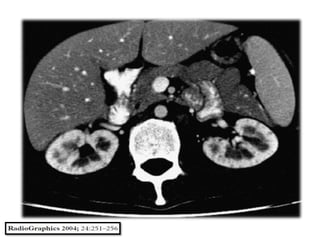

Próstata

La Tuberculosis de la próstata suele ser secundaria a la

infección del tracto urinario superior.

Necrosis, calcificación, necrosis caseosa son las

manifestaciones patológicas comúnmente

encontradas.

Sin embargo, cuando no hay calcificación, la infección

prostática no se pueden distinguir de los abscesos

piógenos.

Además, el antígeno prostático específico (PSA) puede

ser elevada en aproximadamente el tercio de los

pacientes .

Sin antecedentes de afectación de otros órganos por

tuberculosis, el diagnóstico generalmente se obtiene

después de la biopsia.